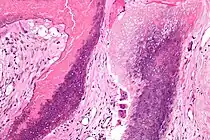

Histopathology of pilomatricoma, high magnification, H&E stain, showing the characteristic components of basaloid cells and ghost cells.

The characteristic components of a pilomatricoma include a stroma of fibrovascular connective tissue surrounding irregularly shaped, lobulated islands containing basaloid cells (being darkly stained, round or elongated, with indistinct cell borders and minimal cytoplasm, with nuclei being round to ovoid, deeply basophilic and generally prominent nucleoli), which abruptly or gradually transitions into ghost cells (having abundant, pale, eosinophilic cytoplasm, well defined cell borders and a central clear area, but only faint traces of nuclear material), which in turn may transition into keratinaceous to amorphous necrosis.[11]

The presence of calcifications with foreign-body giant cells is common within the tumors.[12]